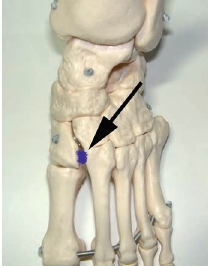

Mittelfußverletzungen im Sport, insbesondere Kapselbandverletzungen, haben in den letzten Jahren zugenommen 1 2 3. Dabei handelt es sich vor allem um Verletzungen des Lisfranc-Bandkomplexes. Der Lisfranc-Ligamentkomplex umfasst einen dorsalen und einen plantaren Anteil. Die Bandzüge verbinden das Os cuneiforme mediale mit der Metatarsale-II-Basis (Abb. 1). Das Ausmaß der Schädigung variiert stark – von der Zerrung bis hin zur vollständigen Zerreißung mit Diastase zwischen dem ersten und zweiten Metatarsale, ggf. auch mit Schädigung der angrenzenden Gelenkfiächen. Die leichteren und mittelschwer ausgeprägten Verletzungen werden häuflg erst verzögert diagnostiziert 4. Nicht selten sind diese Verletzungen Ursache langanhaltender Beschwerden und Sportunfähigkeit.

Der Lisfranc-Bandkomplex spielt eine zentrale Rolle bei der Stabilisierung des Längsgewölbes 38. Eine weitere Besonderheit ist, dass die Basis des Os metatarsale II die anderen Mittelfußknochen nach proximal überragt. Die intermetatarsalen Bänder verbinden vor allem plantar mit sehr kräftigen Zügen die Ossa metatarsale II bis V 39. Zwischen dem ersten und zweiten Strahl gibt es keine intermetatarsalen Bänder 40. Das LisfrancBand spielt deshalb eine entscheidende Rolle in der Stabilisierung der Lisfranc-Gelenklinie. Es entspringt der lateralen Oberfläche des Os cuneiforme mediale. Der plantare Anteil läuft schräg nach plantar und lateral, um an der Basis des Os metatarsale II zu inserieren. Die dorsalen Anteile des Lisfranc-Bandes ziehen fußrückenseitig vom Os cuneiforme mediale zum Os metatarsale II (siehe Abb. 1). Insgesamt sind Verletzungen des Lisfranc-Bandkomplexes selten. In der Literatur wird über eine Häufigkeit von 1 auf 50.000 Personen berichtet 41. Meist ist diese Verletzung dann die Folge von Hochrasanztraumata wie z. B. Verkehrsunfällen und ist kombiniert mit ausgeprägten Zerreißungen von Kapseln und Bändern in der gesamten Lisfranc’schen Gelenklinie 42.